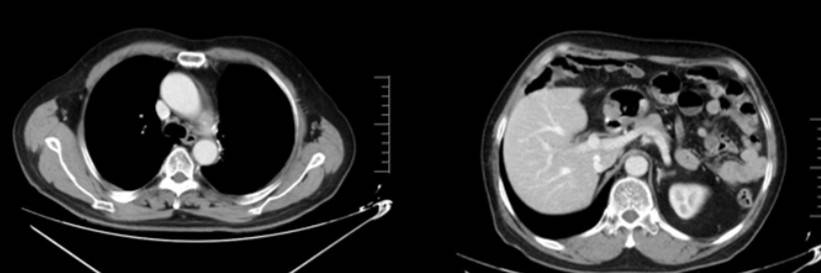

2024年9月19日(11月后):左侧锁骨上区、纵隔及左肺门区多发小淋巴结大致同前,左残肺及右肺小结节灶较前变化不明显;

2024年12月9日(14月后):左残肺及右肺结节较前明显缩小;

2025年8月19日(22月后):左侧锁骨上区、纵隔及左肺门区多发小淋巴结基本同前,未见明确疾病进展迹象。

截至2025年10月,患者已接受芦康沙妥珠单抗治疗超24个月,PFS达24个月以上,仍在持续治疗中,疾病控制稳定。